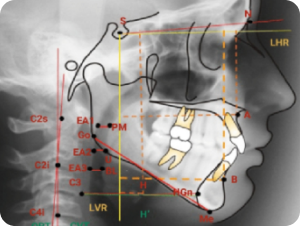

Cephalometric Tracing & Analysis